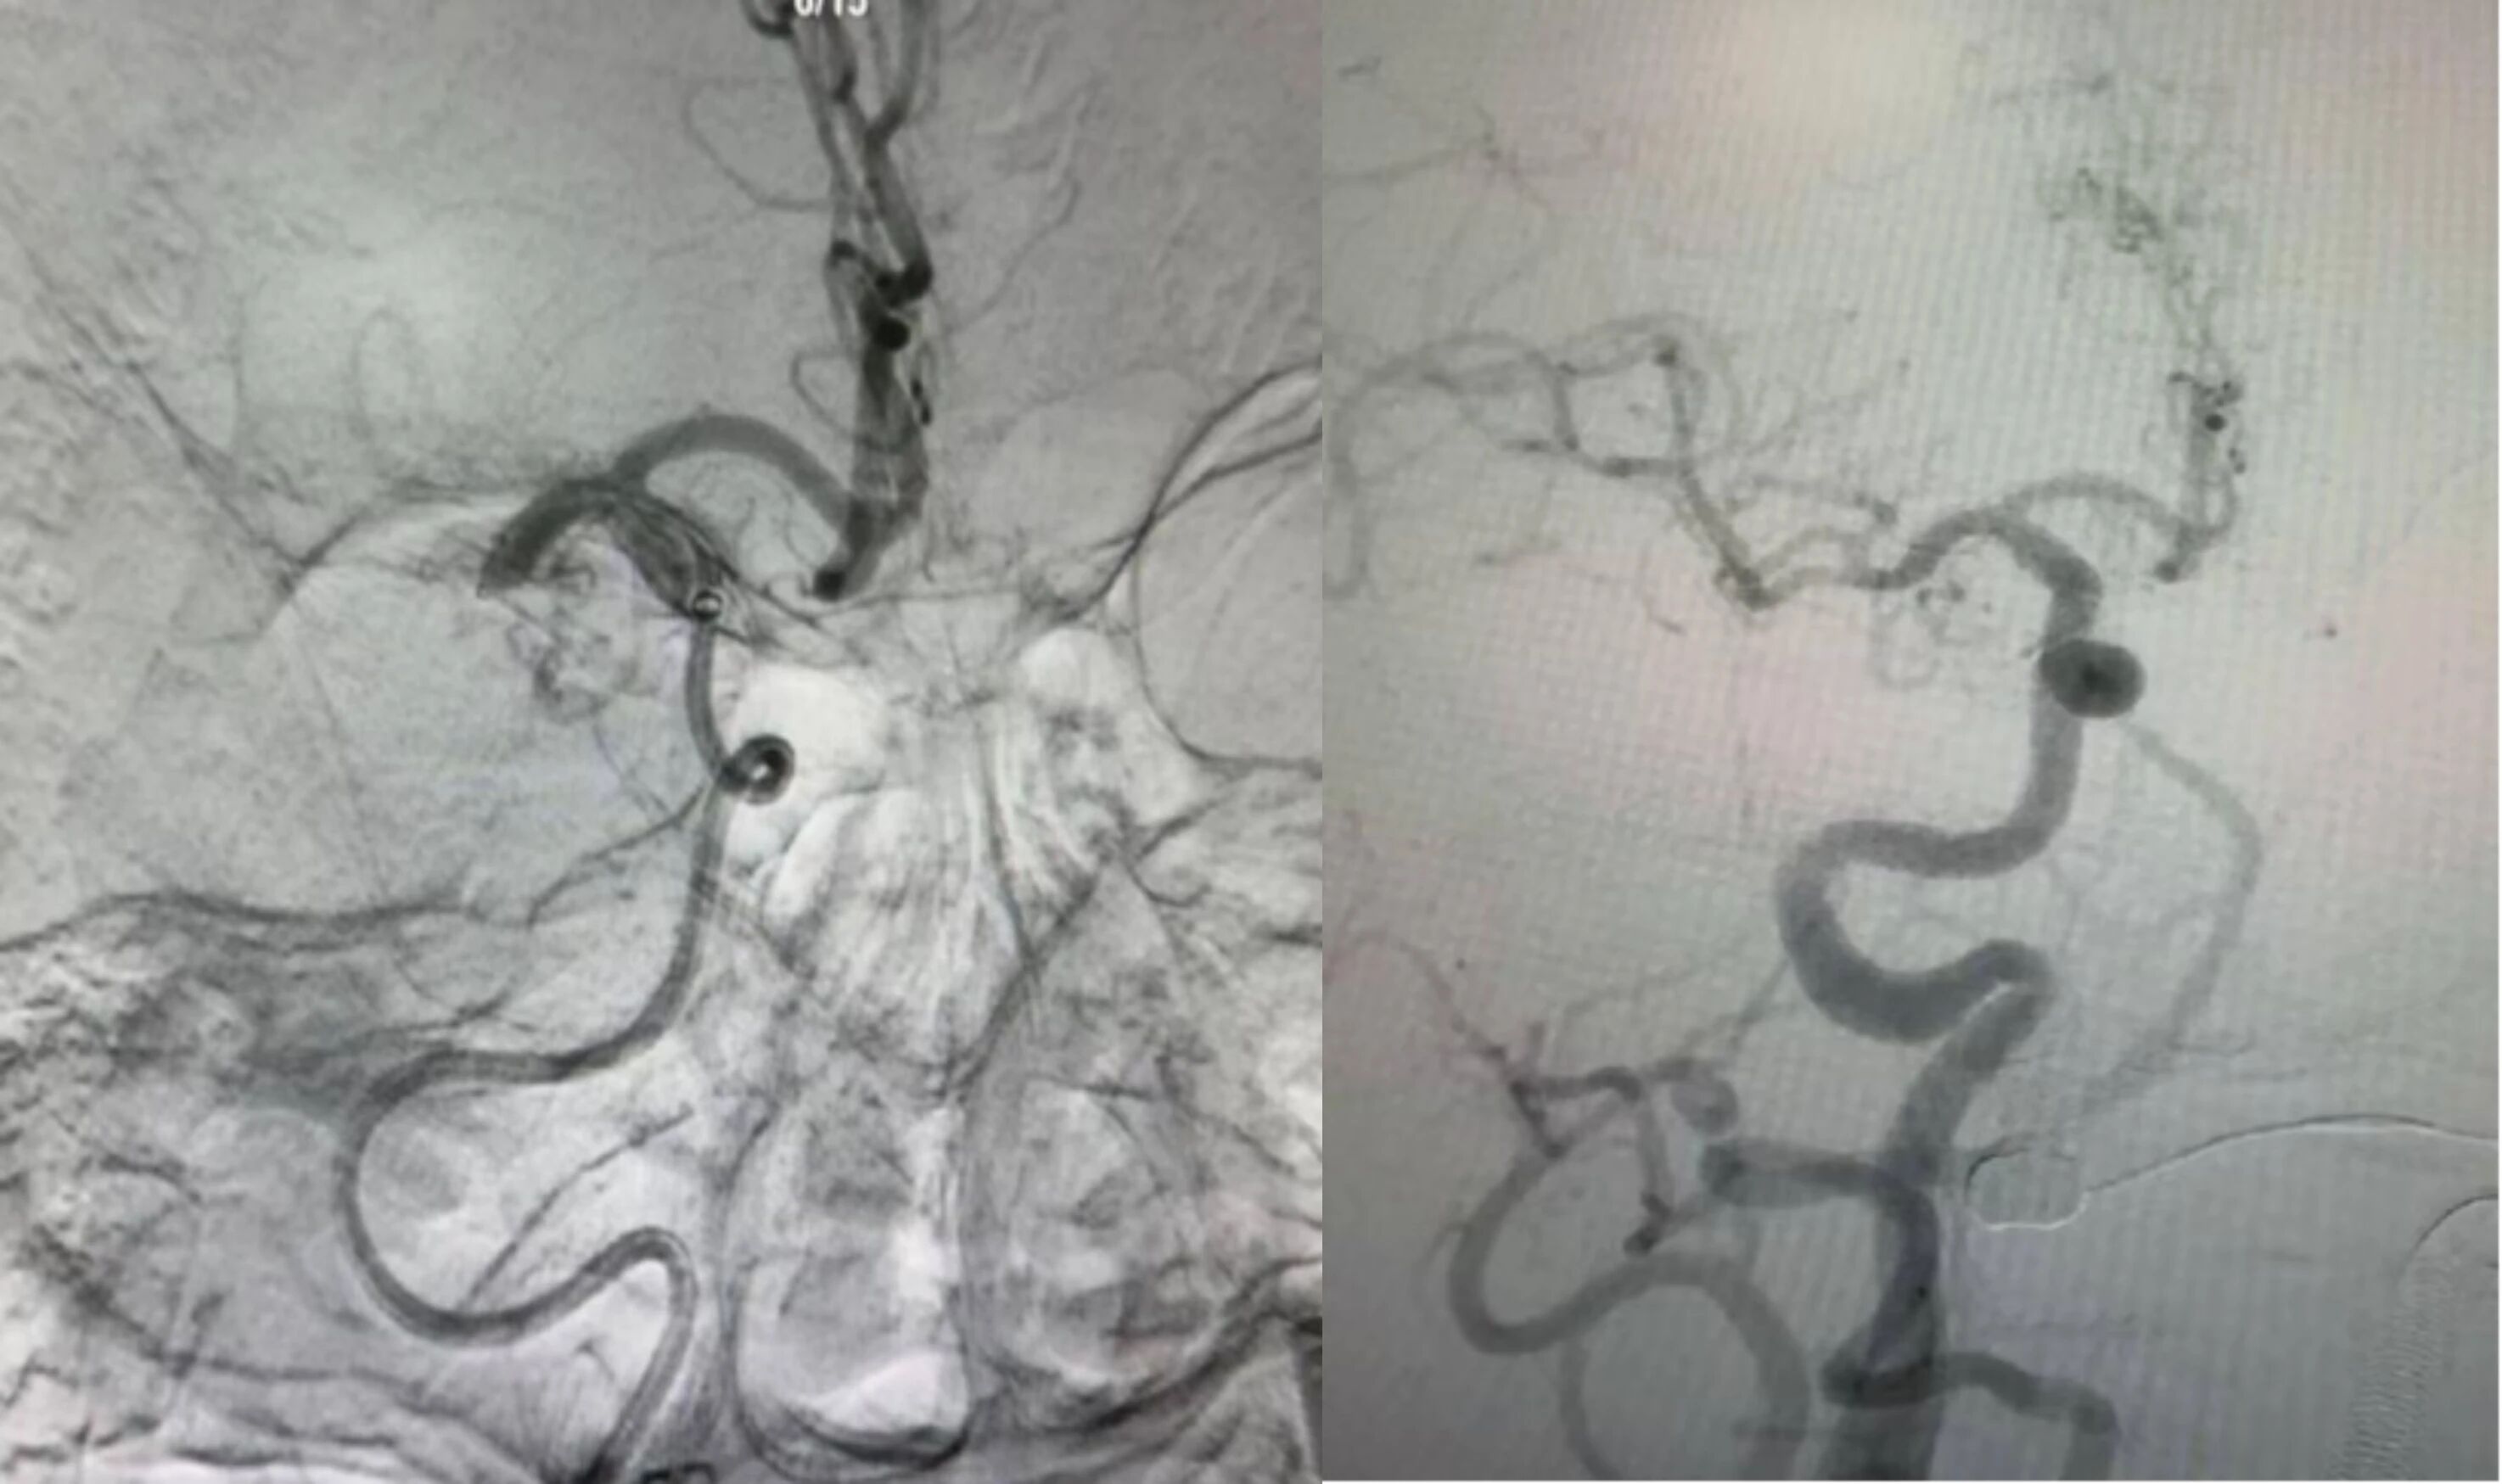

神经内科闵汇刚主任医师当机立断,决定改用桡动脉入路。通过西蒙导管成袢技术,团队成功建立血管通路,运用 SWIM 抽拉结合技术精准取出新鲜血栓。术后复查造影显示闭塞血管完全再通,且无颅内出血等并发症。